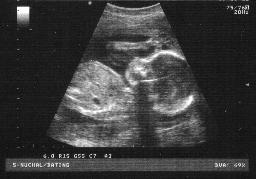

Addicted?: Health care workers say a meth-user's fetus can inherit growth and developmental problems before being born.

Several studies have shown that unborn babies exposed

to meth are likely to suffer low birth weight, slow develop-

ment and probably socializing problems later in life.

A Brown University study found that newborns whose

mothers used meth- amphetamine during pregnancy are 3.5 times more likely to be

born underweight compared to newborns whose mothers

didn’t use the drug.